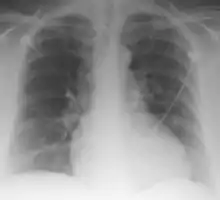

Palla Sign and Westermark Sign | |

Palla's sign is a clinical sign in which an enlarged right descending pulmonary artery is seen on the chest x-ray in patients with pulmonary embolism. It is of low sensitivity, and its specificity is not known. It exhibits as a "sausage" appearance on X-ray. [1] It is named after italian radiologist Antonio Palla. In 1983, he published his observations that close to 25% of patients with pulmonary embolism had a chest x-ray sign of enlarged right descending pulmonary artery.[2][3]